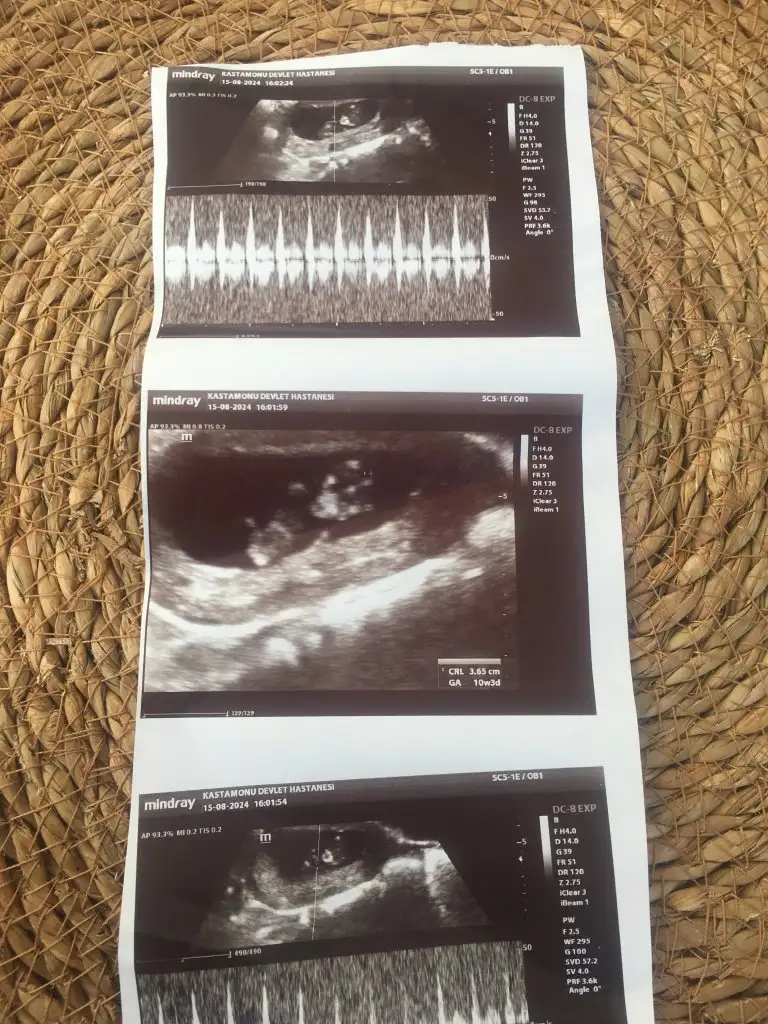

Çok merak ediyorum cinsiyet tahmini yapar mısınız rica etsem

13 haftalık cinsiyet tahmini yapabilir misiniz